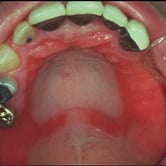

Edentulismo total

Ausencia completa de dientes en una o ambas arcadas, comprometiendo gravemente la masticación y la estética facial.

La falta de dientes también puede causar atrofia ósea acelerada en las mandíbulas.

Los pacientes pueden experimentar dificultades significativas para hablar y comer. Además, la falta de soporte dental puede provocar un aspecto facial envejecido.